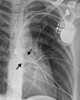

Transposition of great vessels with interatrial communication

Atrial septal defect

Right atrial enlargement

Right-to-left atrial shunt